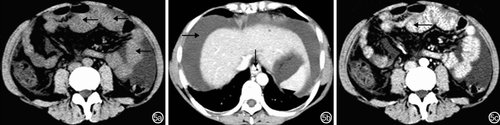

十二指肠癌患者CT检查主要表现为局限性中重度肠壁不均匀性增厚,密度不均匀,局部可见软组织包块,病变肠壁明显不均匀强化(图4);肠外主要表现为肠腔偏心或环形狭窄、直肠周围脂肪间隙消失、腹股沟、腹膜后或肠系膜淋巴结肿大、腹腔积液,回盲部肝转移癌偶尔并发肠套叠和肠梗阻。(点击图片可查看原图)

图4 十二指肠癌患者CT检查特征:十二指肠壁明显不均匀性增厚(←)4a:平扫肠壁密度不均匀;4b:动脉期肠壁明显不均匀强化;4c:静脉期肠壁明显均匀强化

肝硬化门静脉高压症患者CT检查结果主要表现为胃、小肠弥漫性轻度环状向心性增厚、明显不均匀强化;肠外主要表现为肝硬化、脾肿大、食管胃底静脉曲张、腹腔积液(图5)。(点击图片可查看原图)

图5 肝硬化门静脉高压症CT检查特征 5a:平扫小肠壁弥漫性轻度增厚(←);5b:动脉期肝硬化、腹腔积液(→)、食管静脉曲张(↓);5c:静脉期小肠壁增厚且明显不均匀强化(←)